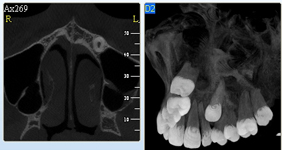

3D DVT - NewTom

Je speciální zubní digitální tříprostorový tomograf (3D), který umožňuje na základě jediného snímkování vytvořit všechny typy RTG zobrazení, které jsou pro lékaře potřebné. Díky používané technologii tzv. „kuželového paprsku“ a speciálním senzorům je výrazně zmenšená dávka záření - o více jak 80% proti klasickému CT vyšetření. To je významné zejména u dětí. Pomocí tohoto přístroje je možné zjisti skutečnou situaci v čelistních kostech pacienta tedy množství kosti - můžeme změřit skutečnou šířku i výšku kosti, i kvalitu kosti (hustotu) v místě uvažované implantace. 3D (tříprostorové) zobrazení umožňuje zvýšit prostorovou představu operatéra ještě před vlastní operací a zároveň pacientovi lépe objasnit a ukázat oblast plánovaného zavedení implantátu.

Pacient „neumí číst“ RTG snímky, ale díky 3D zobrazení vidí „svoji skutečnou čelist“ - např. jak je nízká či úzká, vidí průběh nervu nebo velikost čelistní dutiny, což mu umožní i pochopení nutnosti v některých případech provést pomocné zákroky ještě před vlastním zavedením implantátu (viz. kostní štěp, sinus lift, kostní granulát...).

Vyšetření pomocí tohoto přístroje používáme i ve stomatochirurgii (zlomeniny čelistí, zuby moudrosti, cysty, onemocnění čelistního kloubu), ortodoncii (retinované zuby, nadpočetné zuby), parodontologii atd.